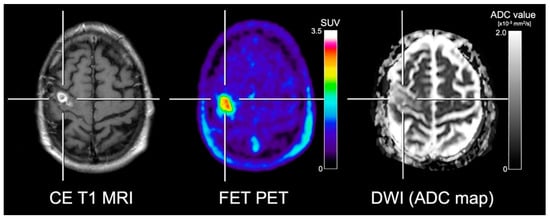

- Karavaeva, E.; Harris, R.J.; Leu, K.; Shabihkhani, M.; Yong, W.H.; Pope, W.B.; Lai, A.; Nghiemphu, P.L.; Liau, L.M.; Chen, W.; et al. Relationship Between [18F]FDOPA PET Uptake, Apparent Diffusion Coefficient (ADC), and Proliferation Rate in Recurrent Malignant Gliomas. Mol. Imaging Biol. 2015, 17, 434–442. [Google Scholar] [CrossRef] [PubMed]

- Rose, S.; Fay, M.; Thomas, P.; Bourgeat, P.; Dowson, N.; Salvado, O.; Gal, Y.; Coulthard, A.; Crozier, S. Correlation of MRI-derived apparent diffusion coefficients in newly diagnosed gliomas with [18F]-fluoro-l-dopa PET: What are we really measuring with minimum ADC? AJNR Am. J. Neuroradiol. 2013, 34, 758–764. [Google Scholar] [CrossRef] [PubMed]

- Choi, H.; Paeng, J.C.; Cheon, G.J.; Park, C.K.; Choi, S.H.; Min, H.S.; Kang, K.W.; Chung, J.K.; Kim, E.E.; Lee, D.S. Correlation of 11C-methionine PET and diffusion-weighted MRI: Is there a complementary diagnostic role for gliomas? Nucl. Med. Commun. 2014, 35, 720–726. [Google Scholar] [CrossRef] [PubMed]

- Popp, I.; Bott, S.; Mix, M.; Oehlke, O.; Schimek-Jasch, T.; Nieder, C.; Nestle, U.; Bock, M.; Yuh, W.T.C.; Meyer, P.T.; et al. Diffusion-weighted MRI and ADC versus FET-PET and GdT1w-MRI for gross tumor volume (GTV) delineation in re-irradiation of recurrent glioblastoma. Radiother. Oncol. 2018. [Google Scholar] [CrossRef]

- Kinoshita, M.; Arita, H.; Okita, Y.; Kagawa, N.; Kishima, H.; Hashimoto, N.; Tanaka, H.; Watanabe, Y.; Shimosegawa, E.; Hatazawa, J.; et al. Comparison of diffusion tensor imaging and (11)C-methionine positron emission tomography for reliable prediction of tumor cell density in gliomas. J. Neurosurg. 2016, 125, 1136–1142. [Google Scholar] [CrossRef]

- Tietze, A.; Boldsen, J.K.; Mouridsen, K.; Ribe, L.; Dyve, S.; Cortnum, S.; Ostergaard, L.; Borghammer, P. Spatial distribution of malignant tissue in gliomas: Correlations of 11C-l-methionine positron emission tomography and perfusion- and diffusion-weighted magnetic resonance imaging. Acta Radiol. 2015, 56, 1135–1144. [Google Scholar] [CrossRef]